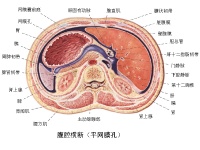

腹腔横断面(通过网膜孔)